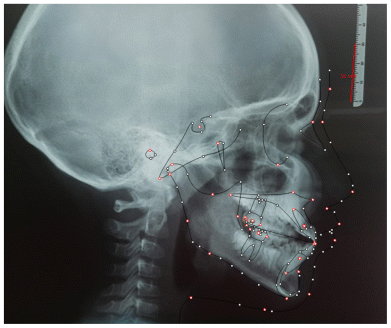

The patient was a young female presenting with a Class III dento-skeletal malocclusion, which was treated using the AMCOP® TC appliance. A comprehensive diagnostic protocol was carried out both before and after treatment, including orthopantomography (Figure 2–3), postero-anterior teleradiography (Figures 4, 5), latero-lateral cephalometric radiography (Figures 6, 7), cephalometric analysis (Tables 1, 2), as well as extraoral (Figures 8, 9) and intraoral photographs (Figures 10, 11). The extraoral examination revealed an edge-to-edge incisal relationship and the presence of a midline diastema. Pre-treatment cephalometric analysis (Deltadent® Lana, Bolzano, Italy) confirmed the diagnosis of a skeletal Class III malocclusion. The treatment plan involved the use of the AMCOP® TC appliance. The patient was instructed to wear the device for two hours in the afternoon and throughout the night for the first six months, followed by nighttime use only for an additional six months. Upon completion of the treatment, the patient achieved a Class I occlusion, with correction of both overjet and overbite. Additionally, the device facilitated tongue re-education and contributed to the postural realignment of the first cervical vertebra.

| Cephalometric Analysis before Treatment | Values (°) | Normal Values (°) |

|---|---|---|

| SNA | 81,3 | 82 ± 3 |

| SNB | 82,9 | 80 ± 3 |

| ANB | −1,6 | 2 ± 2 |

| OVJ | 3.5 | 3.5 ± 2,5 |

| OVB | 0.6 | 2 ± 2,5 |

| CoGoMe | 136,0 | 128,8 ± 4 |

| Is^Ans-Pns | 126,4 | 110 ± 6 |

| Li^GoGn | 106 | 94 ± 7 |

| Apg-Li | 3,6 | 2 ± 2 |

| Cephalometric Analysis after Treatment | Values (°) | Normal Values (°) |

| SNA | 83,0 | 82 ± 3 |

| SNB | 84,0 | 80 ± 3 |

| ANB | 1,0 | 2 ± 2 |

| OVJ | 2,5 | 3.5 ± 2,5 |

| OVB | 1,5 | 2 ± 2,5 |

| CoGoMe | 128,0 | 128,8 ± 4 |

| Is^Ans-Pns | 115,4 | 110 ± 6 |

| Li^GoGn | 99,7 | 94 ± 7 |

| Apg-Li | 2,0 | 2 ± 2 |